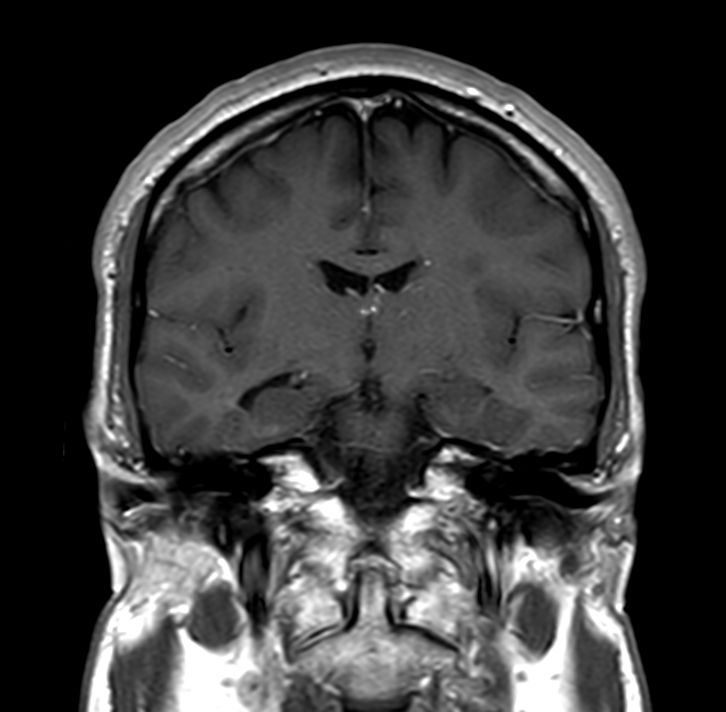

Coronal T1w SEPre-Gado

Coronal T1w SEPost-Gado